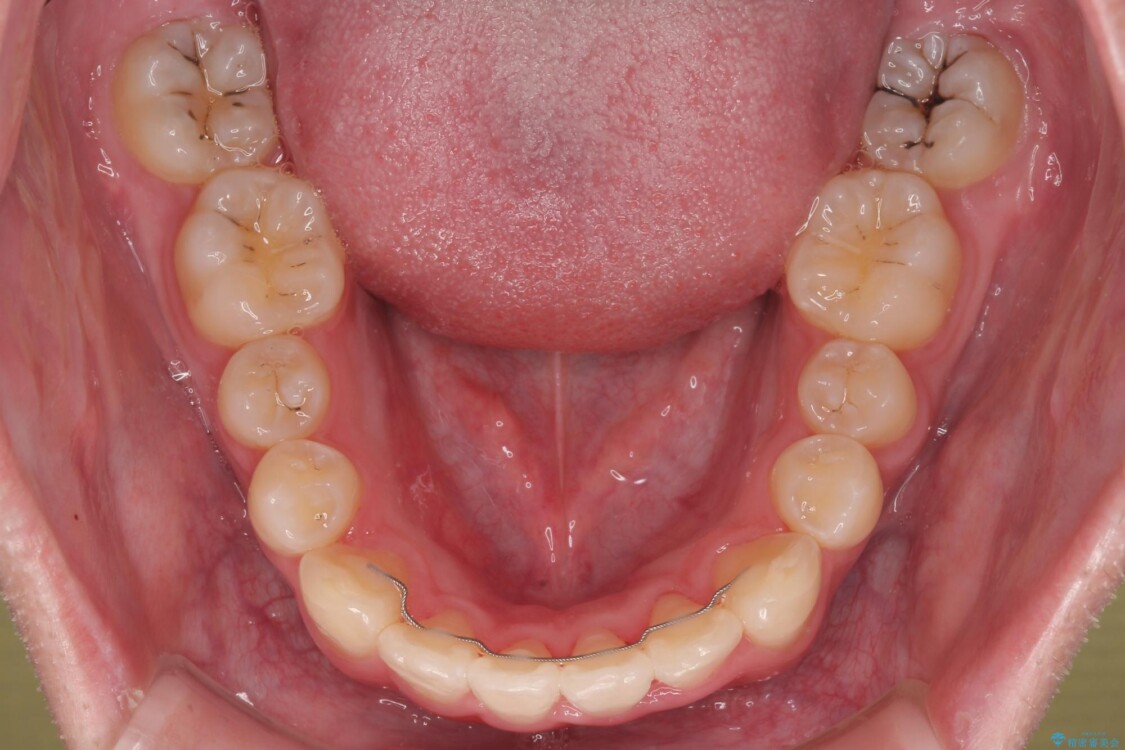

治療後

• 1年でここまで変わる!歯列のがたつきと正中のズレを改善した矯正治療(メタルブラケット×MARPE) 治療後画像

治療後について

適切な診断と装置の選択により、1年という短期間でここまで改善できます。

見た目の美しさだけでなく、将来のむし歯や歯周病リスクを減らすことにもつながる治療です。